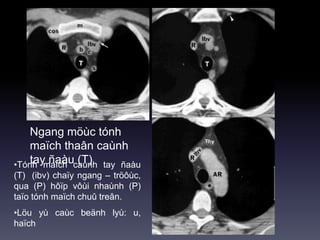

Ngang möùc tónh

maïch thaân caùnh

tay ñaàu (T)•Tónh maïch caùnh tay ñaàu

(T) (ibv) chaïy ngang – tröôùc,

qua (P) hôïp vôùi nhaùnh (P)

taïo tónh maïch chuû treân.

•Löu yù caùc beänh lyù: u,

haïch